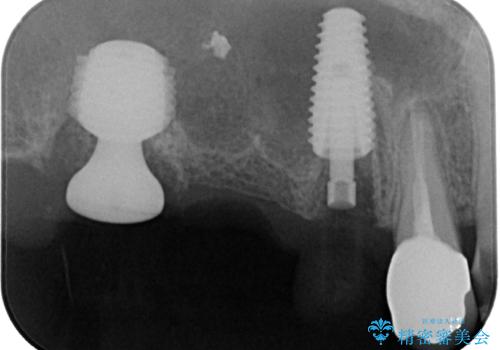

- 土台の歯が割れてしまって、歯がグラグラしているとのことで来院された患者様です。

いずれの歯も抜歯が必要な状態であり、抜歯即時埋入によるインプラント治療を行うこととしました。

右上奥歯は骨欠損の範囲が広いため、抜歯即時埋入は可能であっても、即日で仮歯を装着する即時荷重は難しいと判断されたため、手前の歯まで仮歯を装着することとしました。

術後にインプラントの安定値を測定し、十分な値が達成された後、速やかにセラミッククラウンにて補綴治療を行うこととしました。